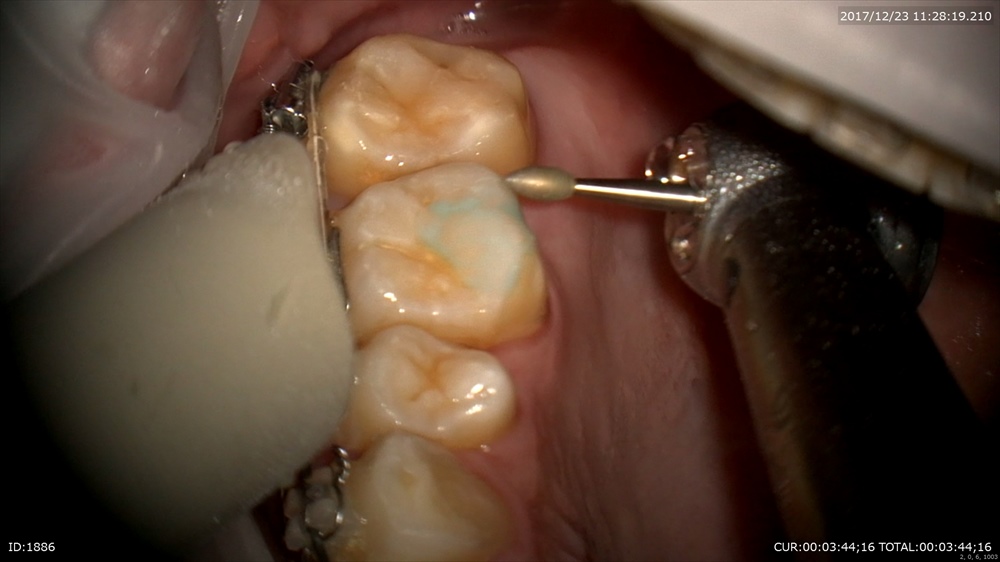

では今日のケース。まず矯正です。

抜歯したスペースが閉じてあともう一歩。お顔が綺麗になりました。男性です。

バイトターボの除去。

来年には終わりますねーー。楽しみ!!